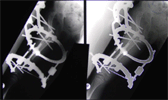

11 years old boy with long standing hip dislocation

Pre

Op

Xrays